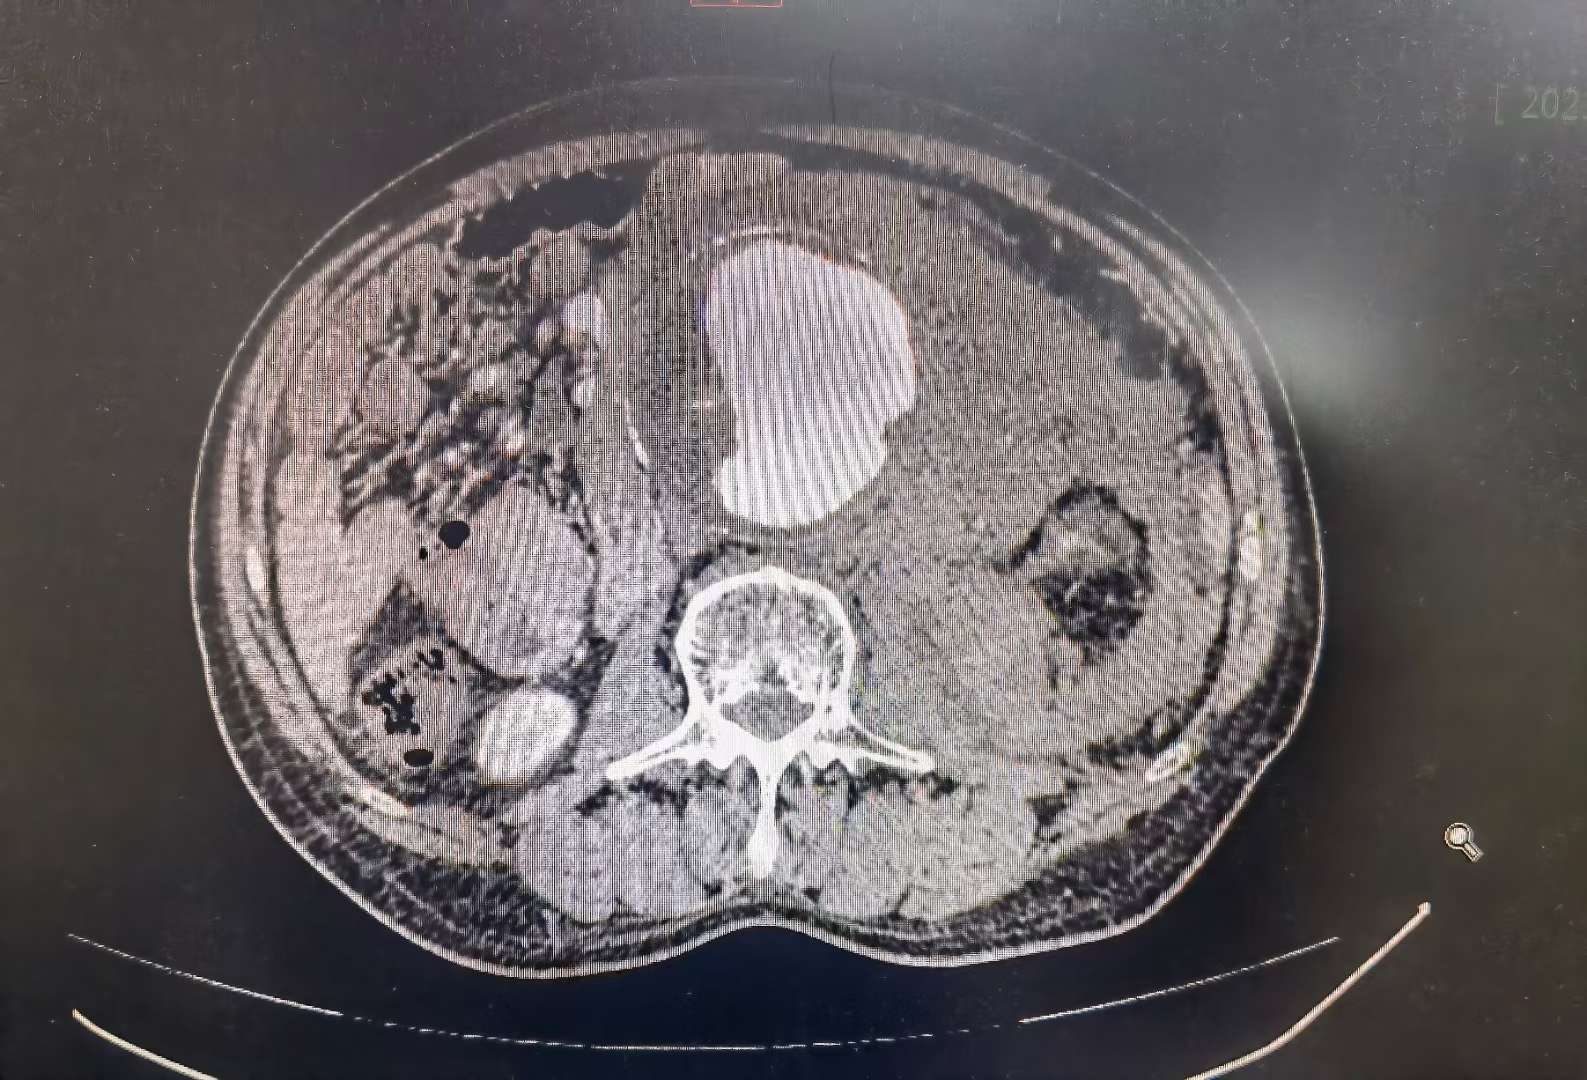

血栓,溃疡斑形成,伴腹腔内腹膜后血肿,考虑腹主动脉瘤破裂(约l2水平)

图片尺寸757x707